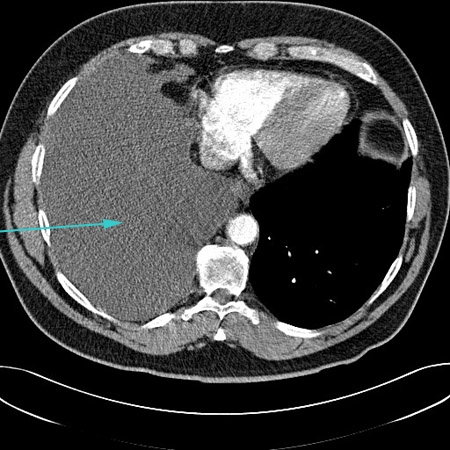

[Figure caption and citation for the preceding image starts]: CT scan showing large right pleural effusionFrom the collection of Dr Nicholas Maskell; used with permission [Citation ends].